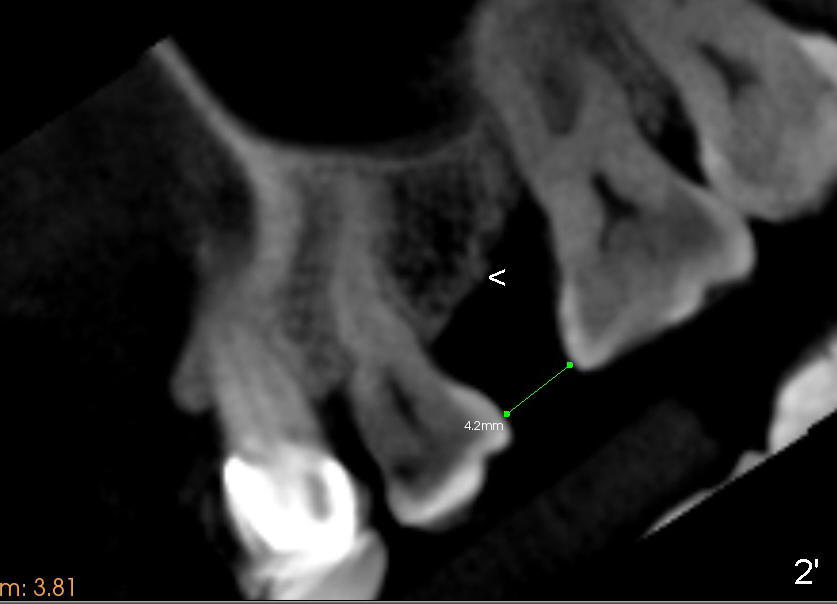

A 39-year-old lady is a dental phobic and finally agrees to restore long-termed missing upper left 2nd premolar (Fig.1). The adjoining teeth tilt toward the edentulous space. To place a 3.8x8 mm submerged implant (Fig.2, CBCT coronal section), enameloplasty is done (compare Fig.1 dashed lines with Fig.3 <). Since the density of the cancellous bone (<100 Hounsfield units (HU)) is much lower than that of the crest (300-400 HU) (Fig.2' <), osteotomy is initiated by 2 mm pilot drill (Fig.3 P) and finished by osteotomes (2 and 3 mm), bone expanders (2.6 mm (Fig.4) and 3.2 mm) and 3.8 mm tap drill. The implant is placed as planned with insertion torque around 35 Ncm (Fig.5). The implant is further lifted into the sinus by 1 mm without bone graft following the last X-ray. A healing abutment (4.1x3) is placed (Fig.6 <).